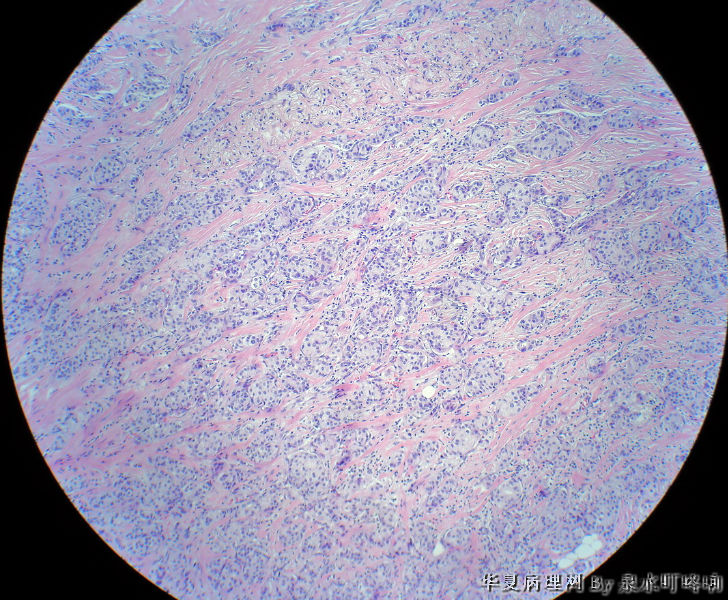

• 右腋下包块图3

图3

最后诊断:浸润性导管癌(分化较低),考虑来自乳腺尾叶或副乳恶变。

女,60岁,右腋下肿物两年余。

大体:灰白带皮组织一块,大小约3.8×2.2×1.4厘米,皮肤呈橘皮样改变,切面灰白,质韧。

首先考虑 乳腺浸润性导管癌 转移,建议进一步免疫组化(CK7、CK20、ER、PR)确诊。